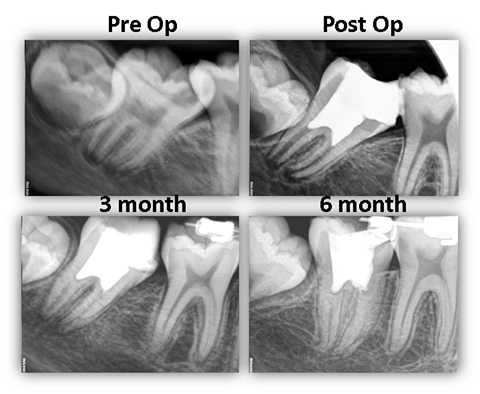

This 13 yo healing male was referred to our office for management of an anticipated carious pulp exposure on tooth #31. The boy’s chief complaint included pain on chewing due to food entrapment within the carious defect and sensitivity to temperature (cold/hot) and sweets. Additionally, this tooth was mesially inclined significantly and was treatment planned for molar uprighting by an orthodontist. The upper left represents the pre-operative radiograph (we apologize for the blurriness as this boy had a slight issue with his gag reflex on this particular day). The upper right depicts the post-operative radiograph where we performed apexogenesis using Brasseler Root Repair Material and glass ionomer as a permanent restoration. The lower left depicts the 1 year recall where the patient remained asymptomatic and we have evidence of continued root development. At this time, the patient had already initiated orthodontic treatment. The final radiograph on the lower right represents 1 year, 6 month recall. We can see that the root has completely developed at this time with significant calcification of the canal system. This may be impactful in the future should the tooth become infected as it would make endodontic treatment very difficult. Additionally, the tooth has been significantly uprighted. The tooth is now primed for full coronal restoration. We have included Oral Surgery in the discussion due to the partial soft tissue impacted 3rd molar (#32) which is slightly visible in all radiographs. We have recommended that an evaluation be made pre-prosthetically to have the 3rd molars removed to aid in restoration of #31. Additionally, the roots have not fully developed yet so extractions would be made easier at this time (panoramic radiograph not included above).